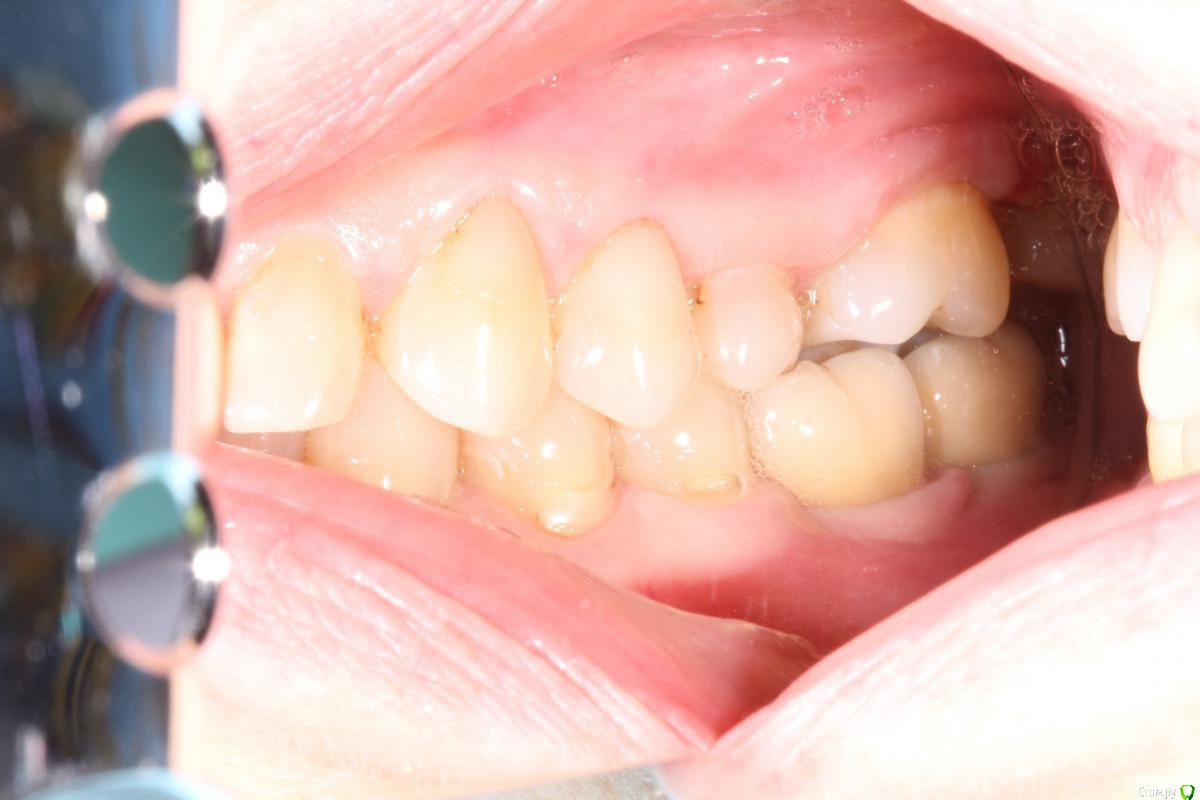

KoroNa Опубликовано 6 мая, 2017 Поделиться Опубликовано 6 мая, 2017 (изменено) У пациента отсутствует 37. Большая скученность фронта н/ч вплоть до премоляров слева. Отсутствует 1 резец, поэтому говорить об удалении зуба чтобы исправить скученное положение зубов не идет. Тонкий фенотип. Хотим дистализировать 3.7, а вслед за ним премоляры. Подскажите лучше это на МИ сделать или же имплант поставить на место 3.6 и за него возможно потянуть? Изменено 6 мая, 2017 пользователем KoroNa Ссылка на комментарий

Yana guapa Опубликовано 7 мая, 2017 Поделиться Опубликовано 7 мая, 2017 (изменено) Подскажите лучше это на МИ сделать или же имплант поставить на место 3.6 и за него возможно потянуть?это решать только Вам (Вы лучше знаете клиническую картину) Винты поставленные в бакл шелф справляются с дистализацией зубного ряда на ура. можете поставить такой винт, к нему сразу начать дистализовать премоляры , а от премоляров дать пружину для апрайта 3.7. (два в одном получите) к премолрам лучше крючок поставить (чтобы вектор тяги шел на уровне центра сопротивления) Изменено 7 мая, 2017 пользователем Yana guapa Ссылка на комментарий

KoroNa Опубликовано 7 мая, 2017 Поделиться Опубликовано 7 мая, 2017 Яна спасибо за вашу оперативную помощь! Завидую вам по доброму, что вы посетили курс по лечению 3го класса) Пока винты Патрисии у нас не сертифицированы вы что крутите?Я ошибку сделала...Нет 37, есть 36.У нас делема. Я предлагаю сразу поставить имплант на место 37 с запасом на дистализация 36,35,34 и за него потом тянуть/ дистализировать. Хирург боится, что имплант выпадет. Поэтому напрашиваются вопросы:1.Могу ли я начать дистализацию на ранних этапах, на мягких дугах дабы не спровоцировать огромнейшую протрузия фронта?2. Не выпадет ли имплант?Или все же Ми лучше?Фото чуть позже скину. Не в городе.... И еще вопрос не по теме. На в/ч почти нет зубов. Планируется большая имплантация. Я буду работать только с низом. Сейчас отправила к ортопеду на изготовление временного сьемного протеза. Мне ТРГ же с протезом делать или без, но без него будут большие погрешности с высотой лица и положение суставных головок из за отсутствия зубов на в/ч Ссылка на комментарий

Yana guapa Опубликовано 7 мая, 2017 Поделиться Опубликовано 7 мая, 2017 Завидую вам по доброму, что вы посетили курс по лечению 3го класса) Пока винты Патрисии у нас не сертифицированы вы что крутите?В видео-роликах Крис Чанга все основные принципы изложены. Винты взяла у Патрисии на семинаре. Я ошибку сделала...Нет 37, есть 36.У нас делема. Я предлагаю сразу поставить имплант на место 37 с запасом на дистализация 36,35,34 и за него потом тянуть/ дистализировать.Имплант не выпадет. НО ....Я думаю, это очень самоуверенно "ставить с запасом ..." . Что Вы будете делать, когда у вас контакты получатся "ни два ни полтора" ?? Я думаю ни хирург ни ортопед Вам спасибо не скажут... Мое мнение - имплант надо ставить когда работа закончена, все контакты приведены в порядок и ортопед дал добро(я уже пару раз так делала - "на глазок", в итоге коронка то крошечная, то огромная, .... и это моя вина, а не ортопеда или хирурга, лучше не допускать таких ошибок) 1.Могу ли я начать дистализацию на ранних этапах, на мягких дугах дабы не спровоцировать огромнейшую протрузия Или все же Ми лучше?Фото чуть позже скину. Не в городе....И еще вопрос не по теме. На в/ч почти нет зубов. Планируется большая имплантация. Я буду работать только с низом. Сейчас отправила к ортопеду на изготовление временного сьемного протеза. Мне ТРГ же с протезом делать или без, но без него будут большие погрешности с высотой лица и положение суставных головок из за отсутствия зубов на в/ч по мне - МИ удобнее, дешевле и ответственности меньше.Если нет МИ с длинной рабочей частью - возьмите обычные винты и поставьте их между премолярами (как анкораж для премоляров), а от премоляров дайте пружину на 3.6. http://i12.pixs.ru/storage/6/7/4/IMG49242JP_7062181_26112674.jpg типа такого принцип 1 Ссылка на комментарий